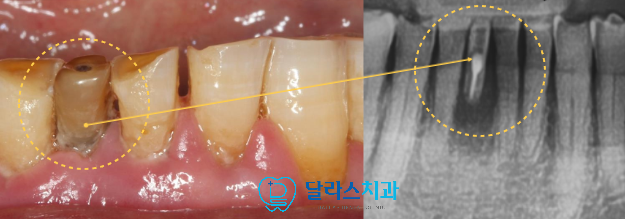

이번 노원치과에 내원하신 환자분은 하악 전치부 치아의 색상이 주변에 비해

심각할 정도로 까맣게 변색이 되어있었고 심한 동요도를 보이고 있었습니다.

X-ray를 촬영해보니 이미 치아의 뿌리부분은 모두 흡수된 상태에서

치조골에 위치해 있지 못하고 거의 떠있는 상황이라

더 이상 자연치 유지가 어려운 상태였습니다.